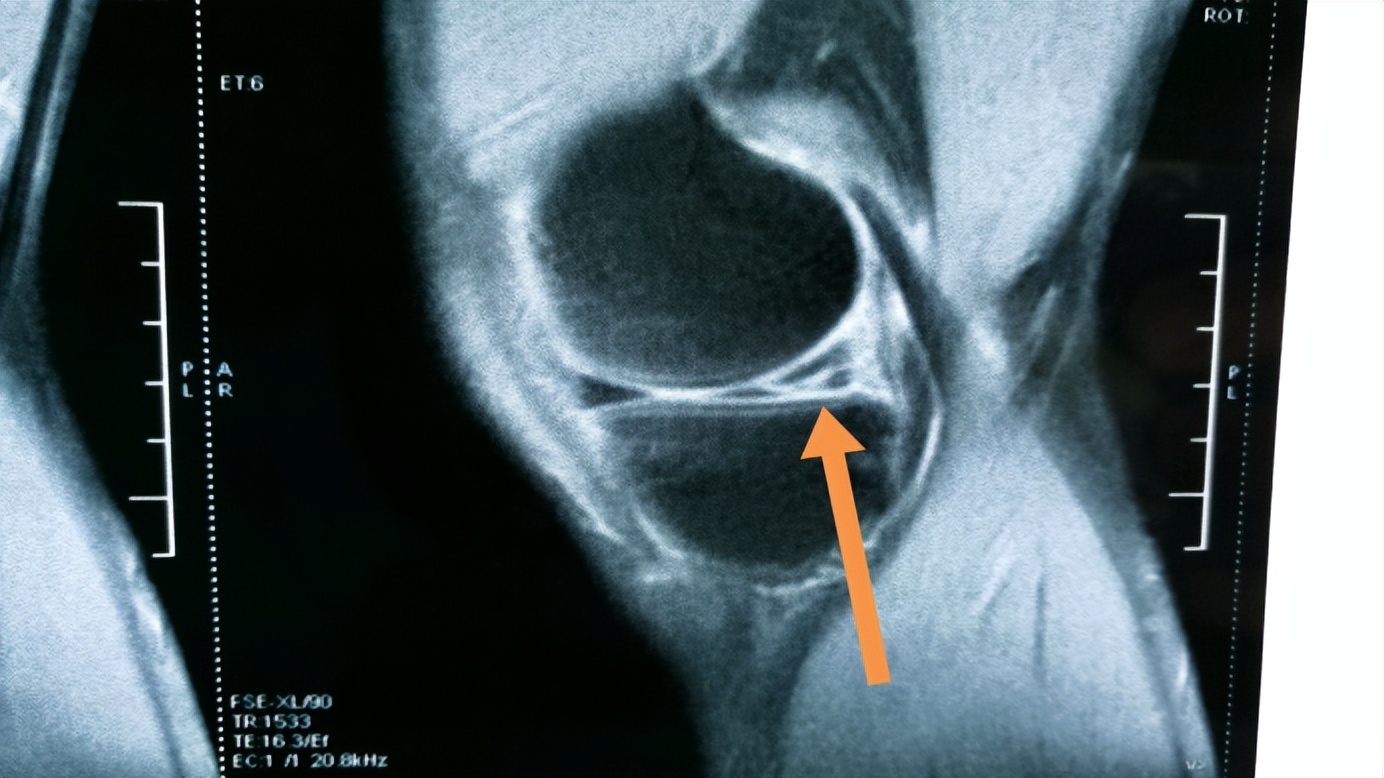

作为人体中的重要关节组织,半月板有着重要的作用。它是人体膝关节软骨组织的一部分,由纤维软骨组成,在胫骨关节上分为内内侧和外侧两部分,因为它的形状类似于半月状,因此叫做半月板。不论是内侧半月板还是外侧半月板,都有着各自的功能,对于半月板检查有着重要的作用。

首先,内侧半月板位于胫骨两个髁之间,与内侧副韧带后部及内侧关节囊紧密相连,正是因为这种紧密的联系,使其前半部分较为固定,活动受限。但是内侧半月板后角与胫骨髁间窝的连接较为松弛,这种一半松弛一半固定的连接方式,致使内侧半月板在受到外力扭转的时候容易产生破裂,导致受伤。

有一种判断半月板是否发生损伤的方式叫做回旋挤压实验中,在该过程中,如果发现患者膝盖内侧有声音,并且伴随痛感,说明内侧半月板可能存在损伤。需要进一步检查,明确判断。

而外侧半月板的与膝关节组织中多处韧带有连接之处,这些韧带的作用便是控制着外侧半月板的活动幅度,起到保护作用。与内侧半月板相比,外侧半月板的活动空间较大,也容易出现损伤。在回旋挤压实验中,如果患者在回旋膝关节并且伸直膝关节的同时,外侧出现声响并且伴随疼痛,说明外侧半月板可能出现损伤。

当患者出现半月板受伤之后,疼痛是典型的症状,因为在半月板滑膜处存在着大量的的末梢感觉神经,当半月板受到外力的挤压发生破裂后,末梢神经受到刺激,就会引发痛感。

除此之外,患者还会伴随肿胀、关节积液的情况,此时患者的发病情况较急、破裂程度较大,引发了出血导致局部出现血肿,也伴随着关节渗出液增多的现象。但是具体是否存在破裂情况以及破裂程度如何还需要通过仪器的进一步检查才能确认。那么,为何会出现半月板损伤的情况呢?